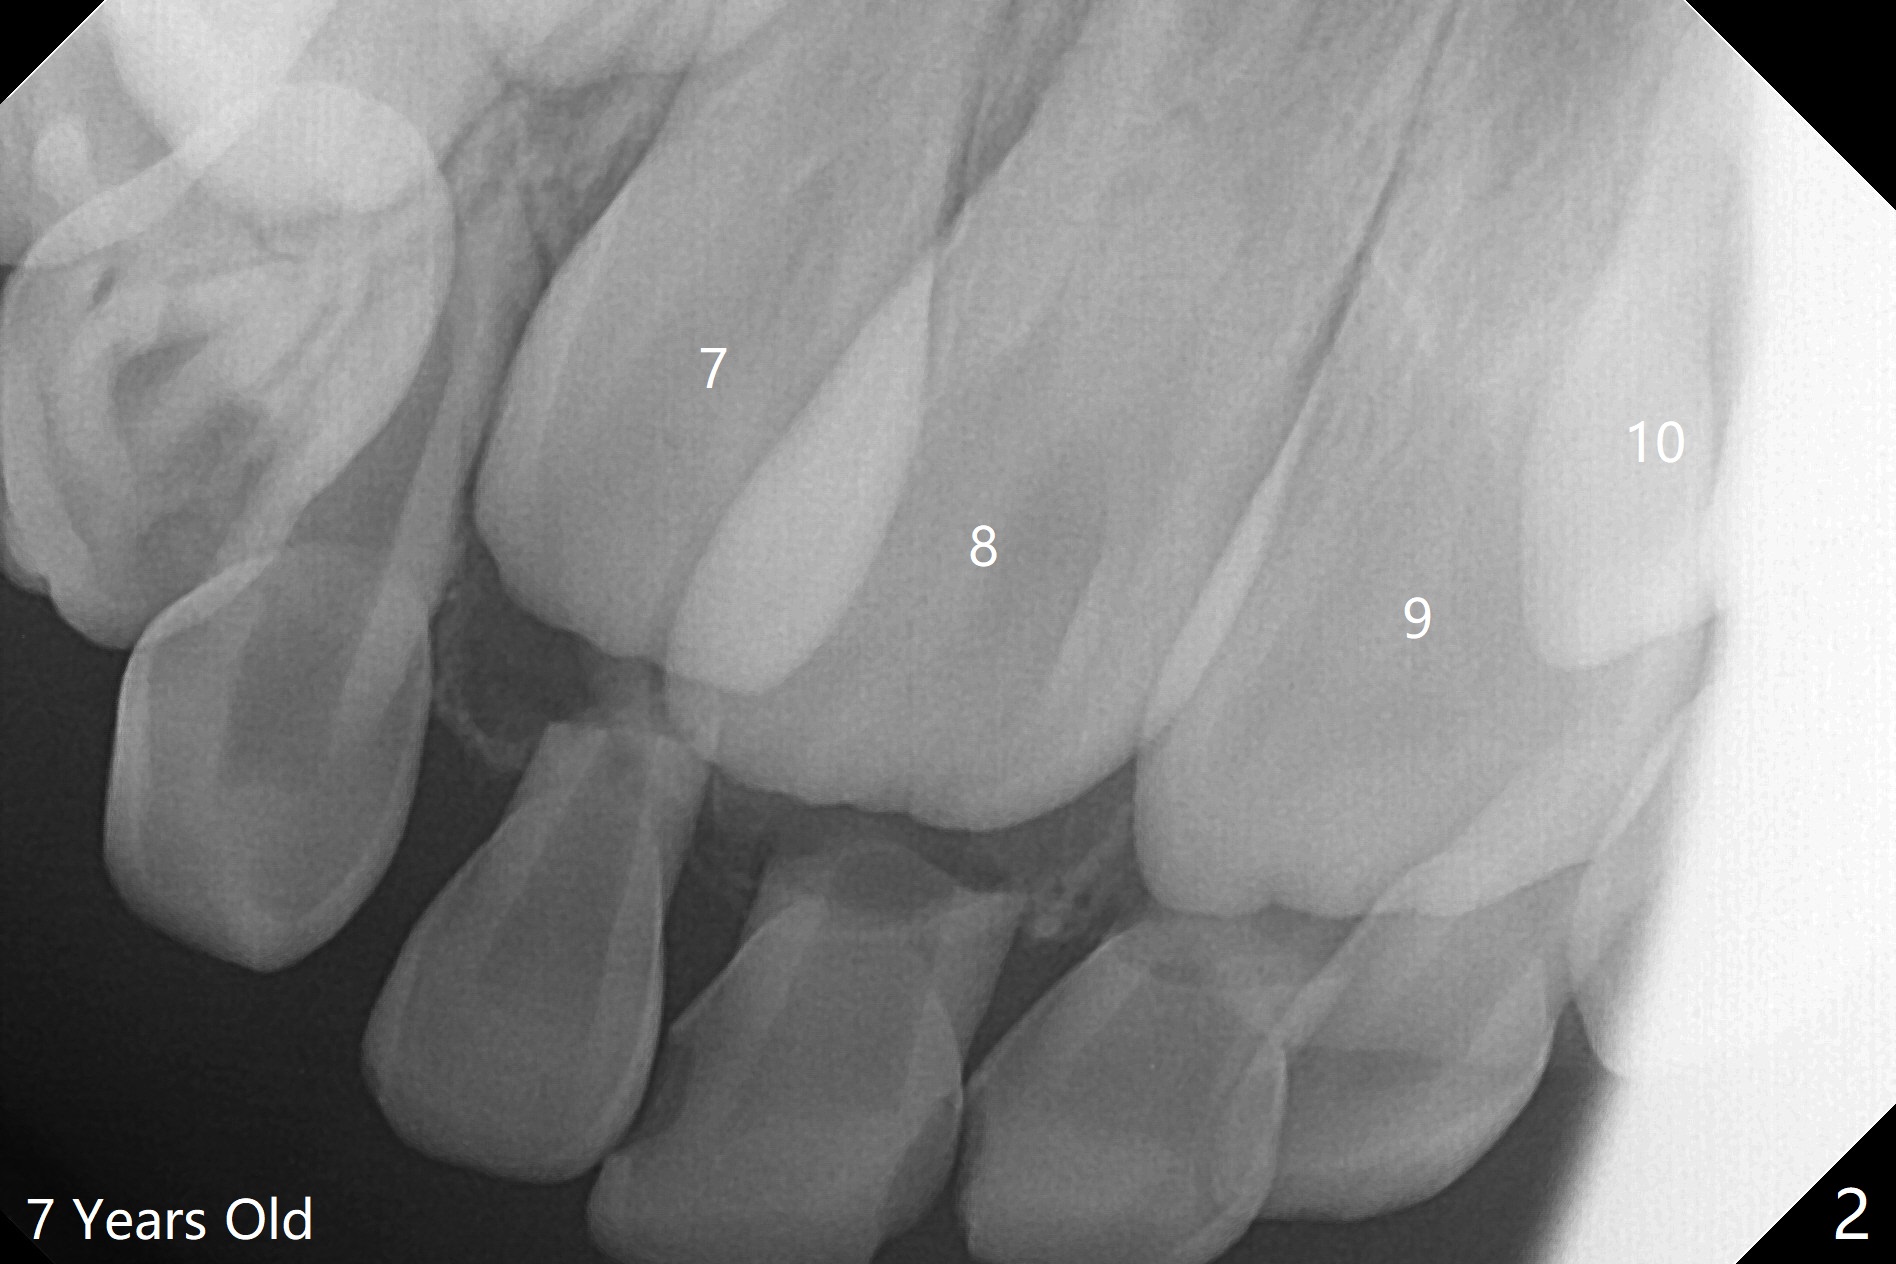

6岁女孩上中切牙发育萌出好像比侧切牙晚(图一),七岁时萌出顺序正常(图二),但是八岁时右上中切牙阻生(图三,四)。似乎拥挤是阻生原因,除了切开助萌之外,扩弓是必要的。不过她口腔卫生欠佳。